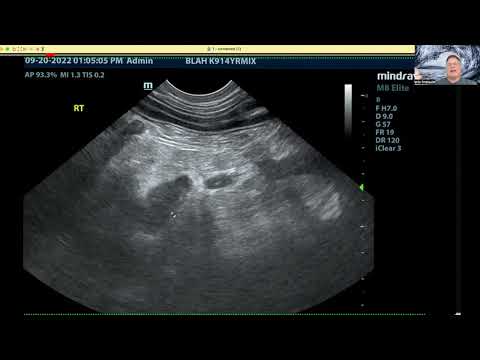

Is this a HCC (LR-5 lesion)? - Hypervascular & washout nodule in a 47-y.o. woman with cirrhosis